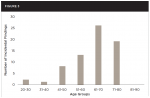

The incidental findings reported were divided into subcategories that included the presence of a periodontal bony defect, periapical radiolucency, residual root, gross caries, internal resorption, odontogenic cyst, radiopaque lesion, and impacted cuspid.The most frequent incidental findings were in the form of periapical radiolucencies (38 instances noted) (Figure 2). As can be seen in Figure 3, which shows the frequency of all incidental findings within each age group, 63 of the 69 incidental findings noted in this study were found in patients aged 41 years or older. Table 1 denotes both the category and number of incidental findings.

Although only 38 occurrences of periapical radiolucencies were noted out of the total 69 incidental findings determined, it should be emphasized that 63 of those 69 (91.3%) incidental findings were in patients aged 41 years or older. Within the group of patients that presented with incidental findings on their CBCTs, some (17) included more than one incidental finding. It should also be noted that 60 out of the 106 patients (56.6%) included in this study did not present with any incidental findings. Categories for this study were standardized by only counting the findings that were obvious on the CBCT. In some instances, it was unclear if something should be counted or not. Because it was a criterion of this study for someone to see that some abnormality was recognized on the 3D scan, whether that be a periapical radiolucency or moderate-to-severe periodontal bony defect, some minimal or possible findings were not included in this study. Examples of each incidental finding are shown in Figure 5 through Figure 12.

Recording a 3D CBCT scan to evaluate a patient's bone during an implant consultation led to the discovery of unintended, incidental findings of which the patient and referring dentist were unaware despite having recent 2D periapical and/or panoramic radiographs taken. That being said, this retrospective, observational study was not conducted to point out or blame the referrer for missing the incidental finding but to demonstrate the advantages of being able to see the entire dentition in three dimensions, which is only made possible through the use of a CBCT scanner. Because of the common occurrence of these unintended findings, the authors were led to the question of the exact amount and frequency of incidental findings found on CBCTs taken for implant consultations. To address this question, a retrospective, observational study evaluating a successive group of patient CBCTs was conducted. In this study, 38 instances of periapical radiolucencies were noted that were not related to, nor were they the reason for taking, the CBCT in preparation for the placement of a future implant. Even though 60 patients did not show any evidence of additional, unintended findings on their CBCT, the authors underscore that 63 of the 69 incidental findings noted were in patients aged 41 years or older. Some of those patients (17) even presented with more than one incidental finding upon analysis of their CBCT. This would suggest and further supports CBCT use for new patients to a general dentist's office when the patient is 41 years of age or older.